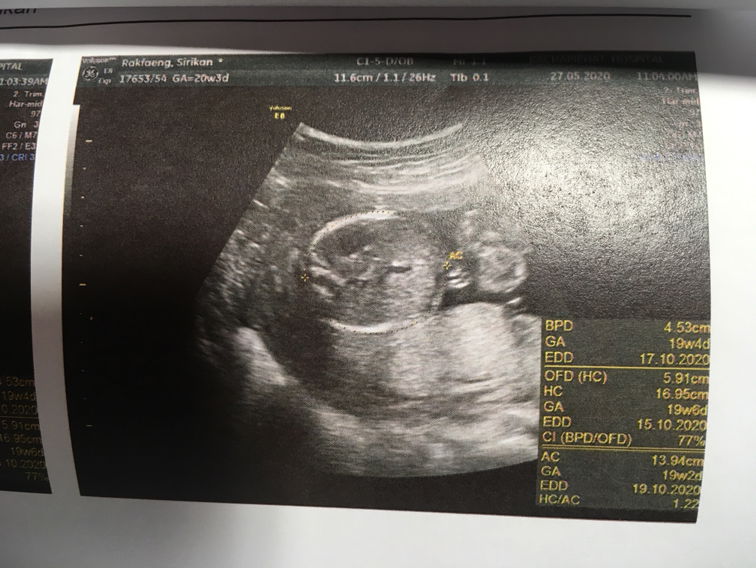

ขอรบกวนแม่ ๆ ช่วยดูหน่อยค่ะ น้องผู้ชายหรือผู้หญิงคะ #21w5d #ขอบคุณล่วงหน้านะคะ 😍😍

ไม่ได้ฟังเสียงหัวใจน้อง ไม่ได้ดูน้องในจอ แม่ตื่นเต้นเก้อเลยนึกว่าจะได้เห็นลูกดุ๊กดิ๊กในจอ หมอบอก ผญ 70% ดีนะแม่ยังพอได้ถามว่าน้องครบไหม สมบูรณ์ไหม ปกติไหม หมอบอกเท่าที่ดูก็ไม่มีอะไร งื้ออออ น้ำหนักตามเกณฑ์ ไว้เดือนหน้าแม่มีตังแม่จะไปซาวด์คลีนิค ยังดีได้รูปมาดู ❤️